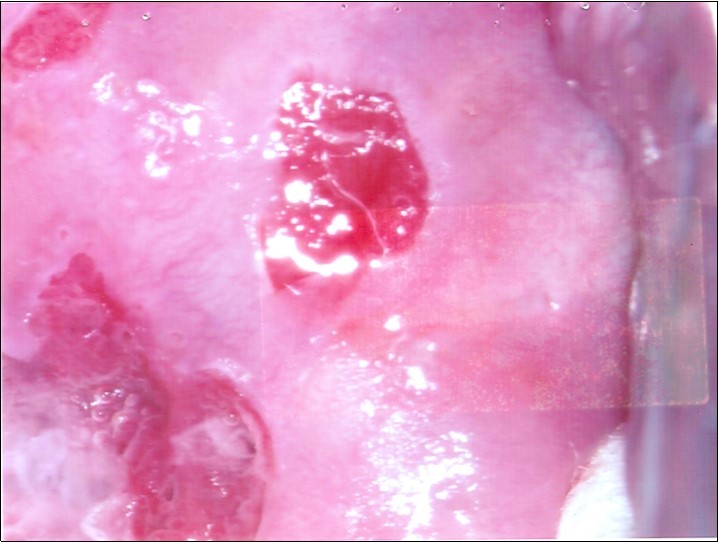

At initial presentation, colposcopy was unsatisfactory due to inadequate visualisation of the transformation zone. (Figure 1) Severe cervico-vaginitis was seen, with frothy white discharge and contact bleeding. A small focus of aceto-white epithelium was seen at the 1 o’clock region surrounded by peeling, friable epithelium. HPV DNA test, as well as cervical punch biopsy of the focus of aceto-white epithelium were taken.

Figure 2a.Repeat colposcopy (low magnification)